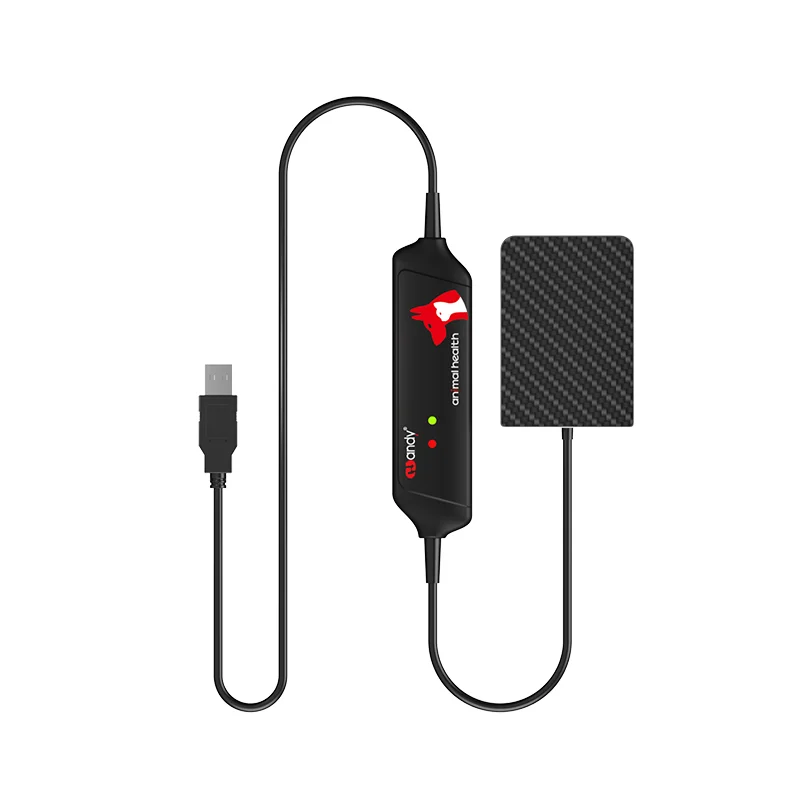

CE Approved Original HANDY Size 4 Dental X Ray Sensor Large Size Veterinary Sensor for Medium and Large Dogs

Model Number | VDR0507-GA0 |

Effective area | 46.7*67.3mm |

Dimensions | 77.1*53.8mm |